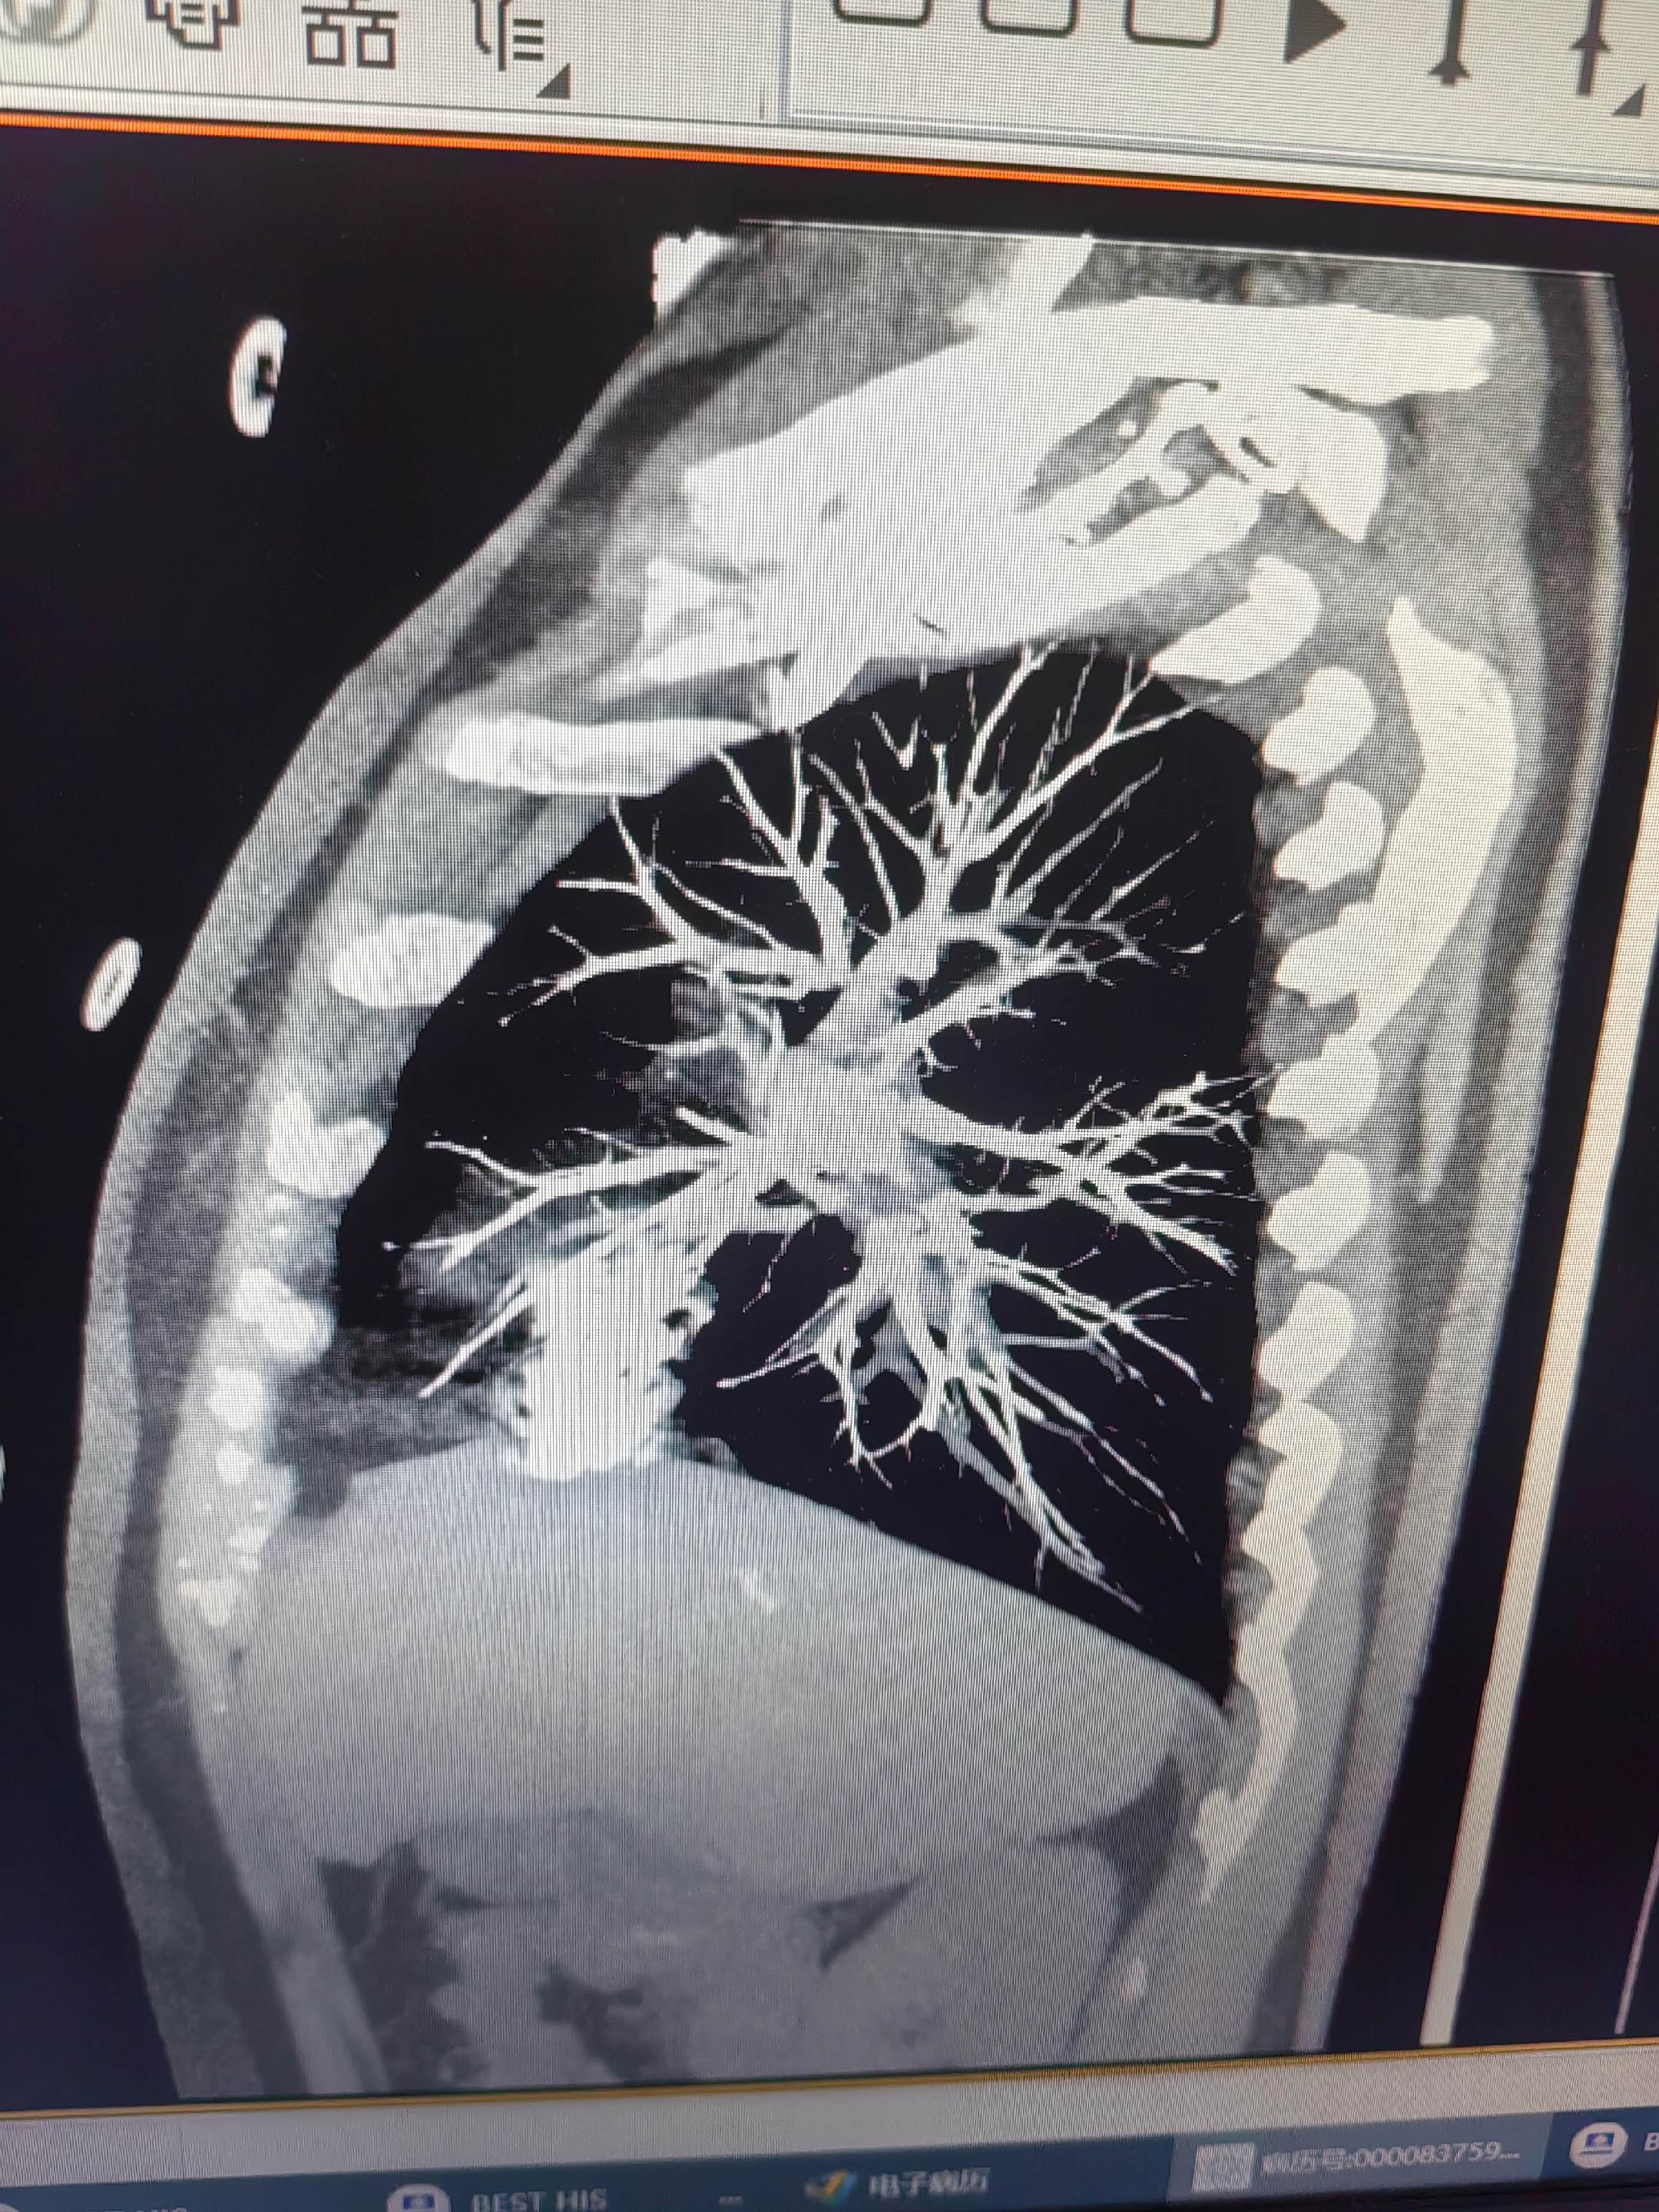

肺栓塞。